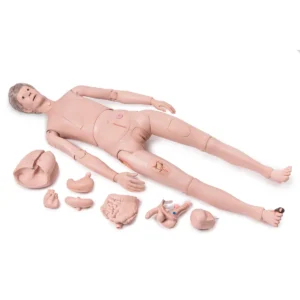

UK 3B Scientific manufacture anatomical models and teaching aids for medical education. 3B Scientific manufacture Medical Simulators, Human anatomy models and charts for universities, schools & health boards.

With competitive value and quality products 3B Scientific equipment has become very popular. Their smart app and other advanced technologies allows students more anatomical information and learning than ever.

Showing 1–30 of 292 resultsSorted by popularity